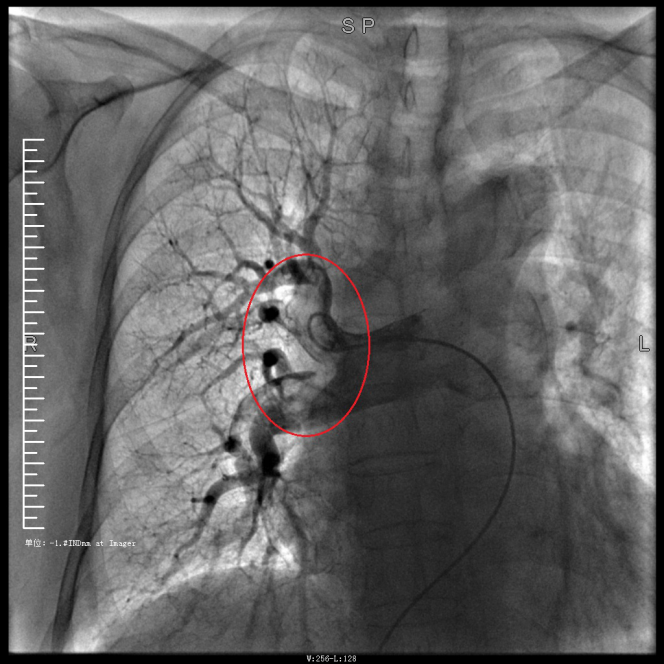

谭婆婆今年已经72岁了,因“突发意识障碍2次”到璧山区人民医院神经内科治疗。谭婆婆没有基础心脏病病史,但近段时间活动耐量明显下降,稍做活动就出现呼吸困难。入院后查BNP及心脏彩超均未提示明显异常,查D二聚体明显升高,经心血管内科周波医师会诊后转入科室继续治疗。在心血管内科主任、内科学(心血管病)博士于长青的指导下,周波医师成功完成医院首例“一站式”微创介入手术。在影像中,可以清晰地看到堵塞的血管经溶栓治疗后,重新畅通无阻,流动起支撑生命的血液。

肺动脉造影技术是目前诊断肺动脉栓塞的“金标准”,在全程心电监护下,通过股静脉或者颈内静脉置入鞘管后,利用导丝引导,将造影导管送入肺动脉;可在左/右肺动脉主干及其左右分支内,分别进行肺动脉造影或选择性肺动脉造影,存在栓塞的肺动脉血管在造影剂注入后即会显示出充盈缺损、充盈缓慢、或者血管显影模糊,严重栓塞的肺动脉血管甚至会出现血流截断征象。

肺动脉导管局部置管溶栓术是通过肺动脉造影确定堵塞的肺动脉部位,然后导管尖端置于血栓处,将尿激酶、链激酶或重组组织型纤维蛋白溶酶原激活剂直接注入血栓处,新鲜血栓在足量的溶栓剂作用下溶解。肺动脉内局部用药特别是小剂量时可减少出血并发症。

注明:第一张、第二张为术前图像